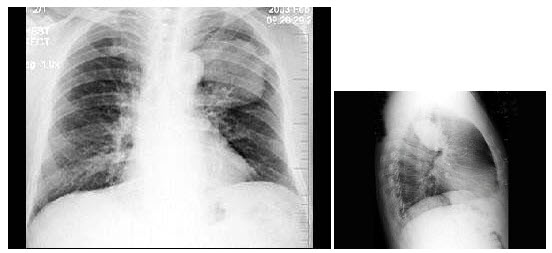

16、单项选择题

男,32岁,2天前被人踢伤胸部,感胸闷、呼吸困难,X线检查如图,最可能的诊断为()

A.左侧气胸

B.左侧胸腔积液

C.左侧胸膜肥厚

D.左侧液气胸

E.左侧肺挫伤